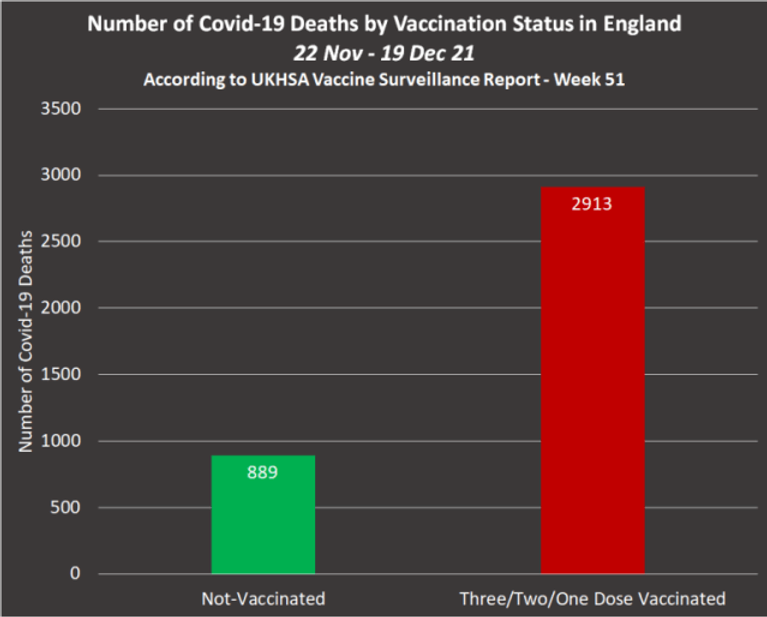

According to the ‘Week 51 – 2021 – Vaccine Surveillance Report‘, the total number of alleged Covid-19 deaths by vaccination status between November 22nd and December 19th, as confirmed by table 10 were as follows –

1. Nonvaccinated population = 889 deaths

2. Partly vaccinated population = 117 deaths

3. Triple/Double-vaccinated population = 2,796 deaths

Source – Page 40 –https://assets.publishing.service.gov.uk/government/uploads/system/uploads/attachment_data/file/1043608/Vaccine_surveillance_report_-_week_51.pdf

This equated to the vaccinated population accounting for 77% of Covid-19 deaths between November 22nd and December 19th and reveals that the number of Covid-19 deaths among the entire vaccinated population was 207 less than the total number of Covid-19 deaths recorded among the triple vaccinated population alone between 24th Jan and 20th Feb 22.

Deaths among the nonvaccinated have fallen from 889 between 22nd Nov and 19th Dec 21, to 559 between 24th Jan and 20th Feb 22. This represents a 37% decrease in overall deaths.

But deaths of the vaccinated population have increased from 2,913 between 22nd of November and 19th of December, 2021, to 4,302 between 24th of January and the 20th of February, 2022. This represents a 48% increase in overall deaths.